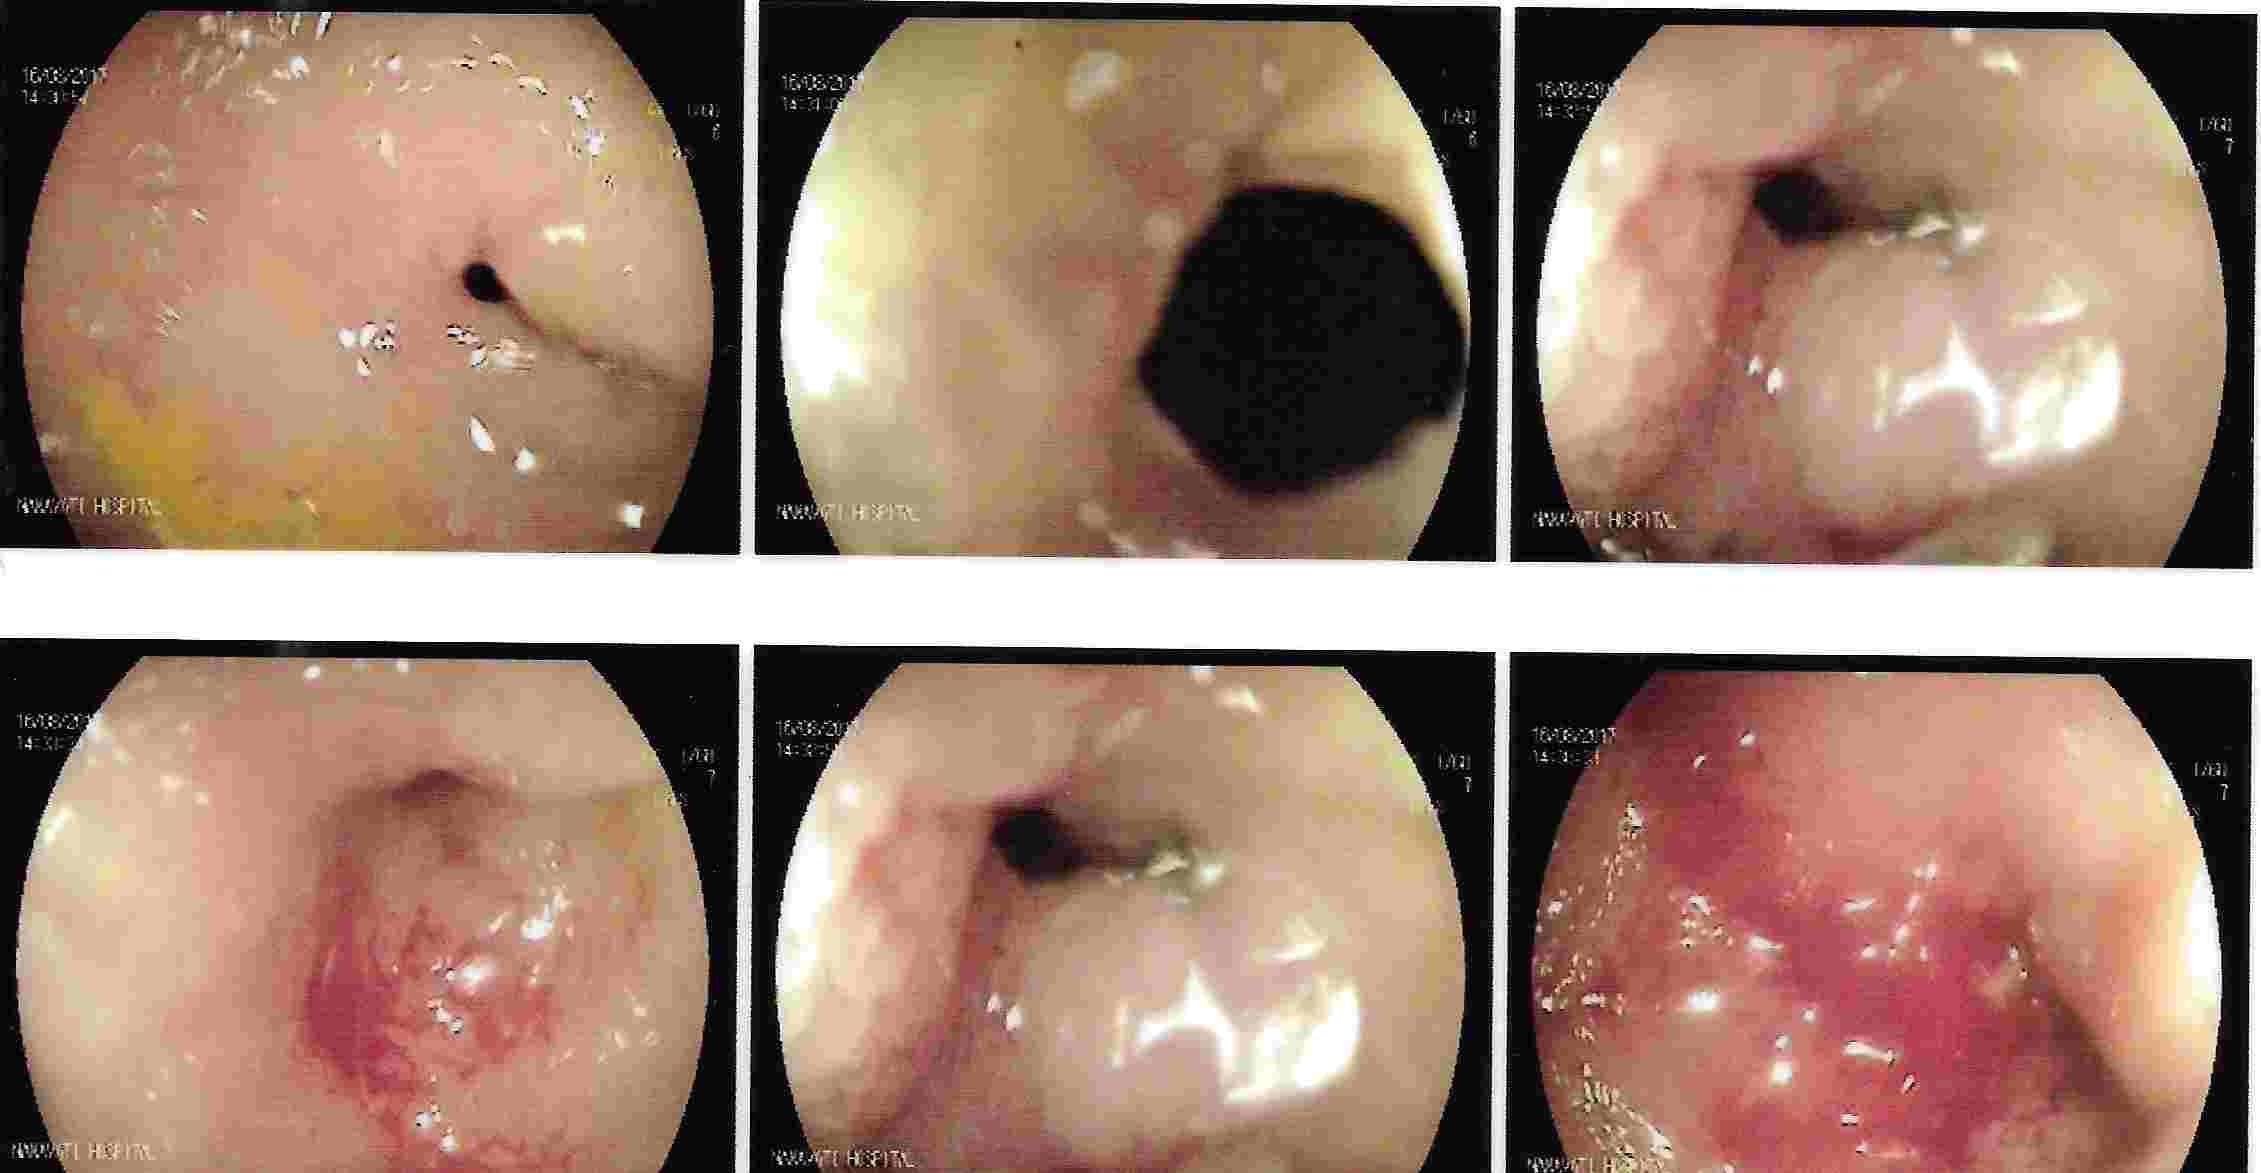

Strong contractions of the food pipe is known as dysmotility of esophagus and an unusual condition known

as Achalasia Cardia due to powerful contraction of the valve of the esophagus at its lower end which

can cause difficulty in swallowing.

Achalasia Cardia - Balloon Dilatation

Achalasia Cardia - Balloon Dilatation

Achalasia Cardia - Balloon Dilatation

Achalasia Cardia - Balloon Dilatation